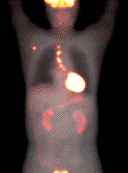

7、PET检查 全身正电子发射体层像(PET)可以发现意料不到的胸外转移灶,能够使术前定期更为精确。胸外转移病例中无假阳性率,但是在纵隔内肉芽肿或其他炎性淋巴结病变中PET检查有假阳性发现需经细胞学或活检证实。